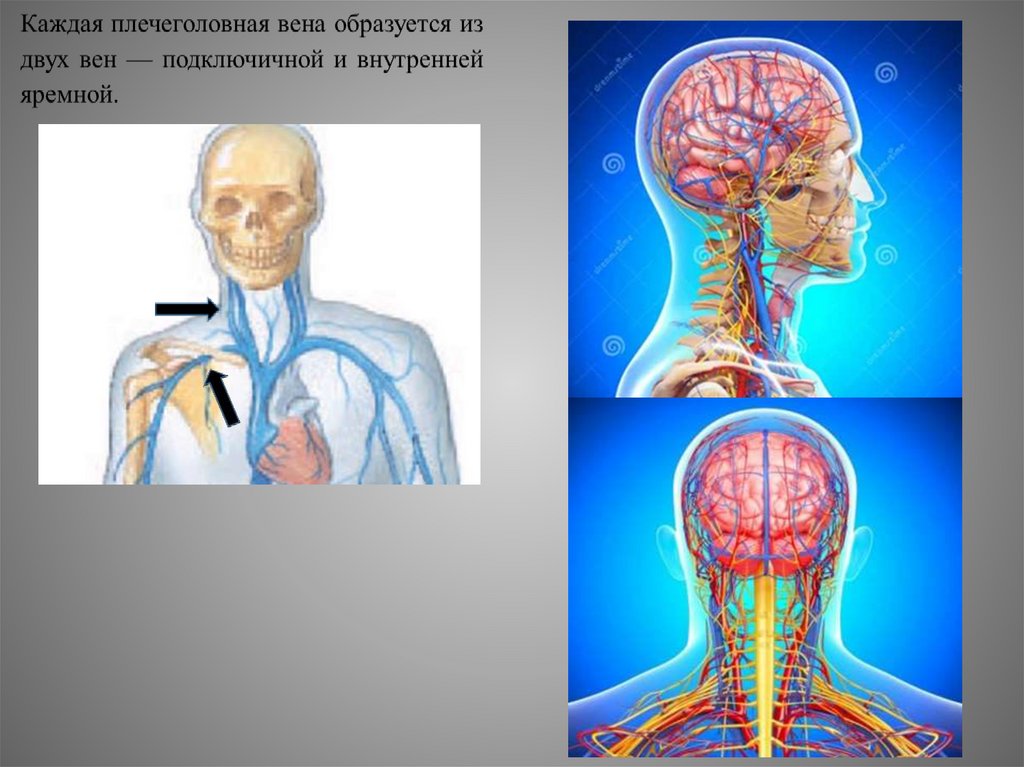

Анатомия внутренней яремной вены: КТ изображения